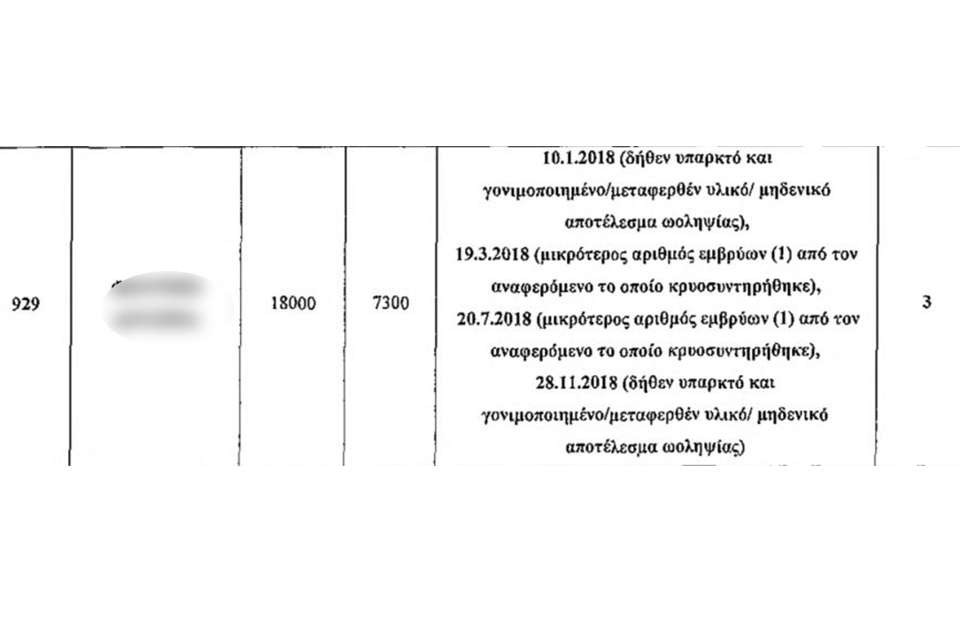

Αν και το ζευγάρι είχε προχωρήσει σε 7 συνολικά διαδικασίες εξωσωματικής γονιμοποίησης από το 2014, το δικαστήριο ασχολήθηκε με τέσσερις περιπτώσεις που αφορούν στο 2018 και εντοπίστηκαν από την αστυνομική έρευνα. Το ζευγάρι, συγκαταλέγεται στους 180 παθόντες των 300 εικονικών – ψευδών ιατρικών πράξεων, 200 από τις οποίες ήταν εντελώς ανύπαρκτες.

Μόνο το έτος 2018, υποβλήθηκαν σε τέσσερις εμβρυομεταφορές λαμβάνοντας από τους υπεύθυνους ψευδή REPORT την ώρα που τα αληθή αρχεία τηρούνταν στα φύλλα εργαστηρίου IVF/ICSI LABOARATORY SHEET όπου οι Αρχές απέκτησαν πρόσβαση μετά την προφυλάκιση των δύο φερόμενων αρχηγών για την υπόθεση με τις παρένθετες, τον Αύγουστο του 2023.